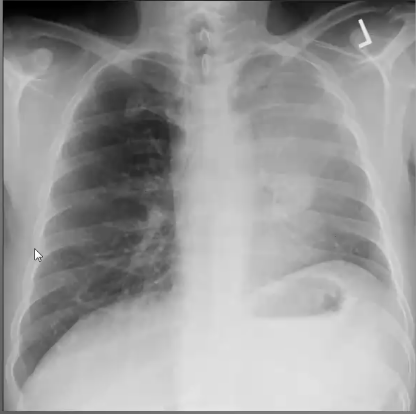

What’s your diagnosis?

Left lingula pneumonia because loss of left heart border (silouhette sign)